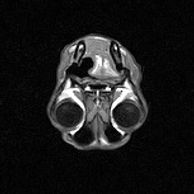

Se realiza RESONANCIA MAGNÉTICA y análisis LCR en H. V. Vetsia, no  observándose imágenes patológicas y con LCR: 20 células / mm3, predominancia de linfocitos y en menor número monocitos. Pt= 33 mg/dl.

Según historial, reseña y pruebas diagnósticas se diagnostica una MENINGOENCEFALOMIELITIS GRANULOMATOSA, englobada dentro de las Meningoencefalitis de Origen Desconocido (MOD). El único modo de realizar un diagnóstico definitivo en este tipo de patologías es mediante biopsia cerebral. En este caso no se realizó, aunque se descartaron el resto de ME (M. necrotizante, leucoencefalitis necrotizante, meningitis – arteritis que responde a corticoides, meningitis eosinofílica) por ser menos compatibles.